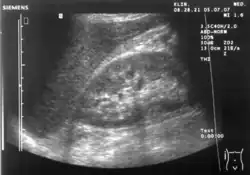

Renal ultrasonography

Ultrasonography of the kidneys is essential in the diagnosis and management of kidney-related diseases. The kidneys are easily examined, and most pathological changes in the kidneys are distinguishable with ultrasound.[7]